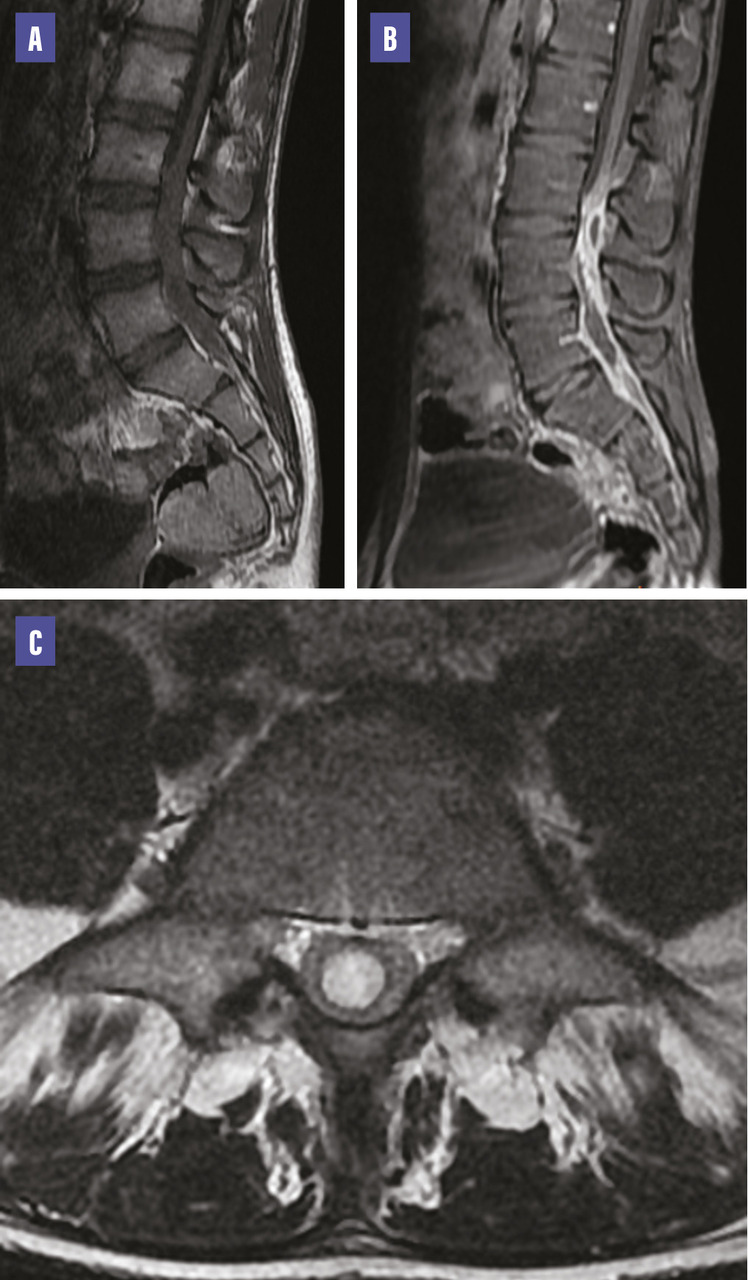

Un jeune homme de 19 ans, sans antécédents médicaux significatifs, se présente aux urgences pour des douleurs au niveau lombaire persistant depuis deux mois, associées à de la fièvre. À l’examen clinique, il est conscient, stable sur les plans hémodynamique et respiratoire, avec un examen neurologique normal mais des signes de syndrome rachidien lombaire. Les résultats biologiques révèlent un syndrome infectieux, avec une leucocytose à 20 000/mm³, une protéine C-réactive (CRP) élevée à 170 mg/L. La ponction lombaire met en évidence une cytologie inflammatoire, une hypoglucorachie et une hypoprotéinorachie. Les cultures bactériologiques sont négatives. L’imagerie par résonance magnétique (IRM) confirme la présence d’un abcès intradural en regard des vertèbres L4 et L5 (figure ). Le patient est traité par antibiotiques (ceftriaxone 6 g/j et métronidazole 500 mg toutes les huit heures pendant 21 jours), avec une évolution favorable, confirmée par une IRM de contrôle. La porte d’entrée de l’infection n’a pas été retrouvée malgré un bilan complet.